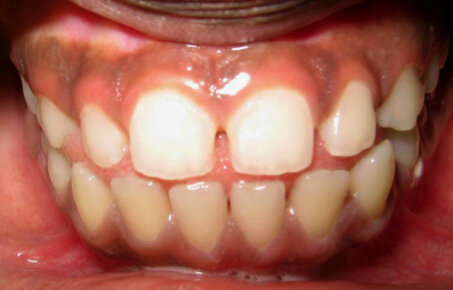

2024.01.08

활짝 웃을 때

앞니 사이 벌어짐이 관찰되었고

코끝과 턱끝을 이은 선을 기준으로

진단해보니 입술의 돌출이 있습니다.

앞니 사이 벌어짐 과 함께

입술 쪽으로 뻐드러진 각도마저 관찰된다면

혀내밀기 습관을 가진 환자의 전형적인

앞니 형태라 볼 수 있습니다.

혀의 강한 힘에 의해 튀어나온 아랫니가

절단교합과 반대교합까지 유발할 수 있습니다.